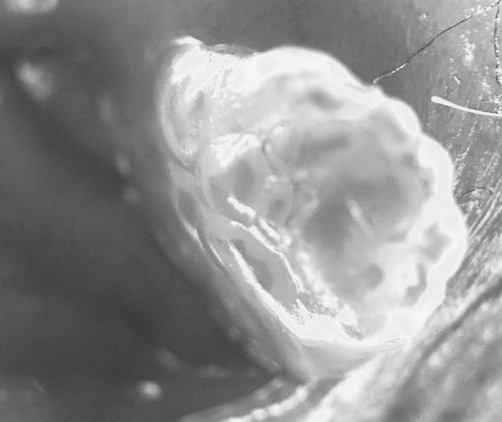

곤지름 방치 후 자연치유 될 확률은 얼마나 될까?

곤지름 방치 후 자연치유 될 확률은 얼마나 될까? 곤지름 진단을 받은 후 혼자 고민하다가 이런 생각 해보...

곤지름 방치하면 자연치유가 된다? 면역력이 관건입니다!

곤지름 방치하면 자연치유가 된다? 면역력이 관건입니다! 안녕하세요! HPV만을 26년간 연구 및 진료한 ...